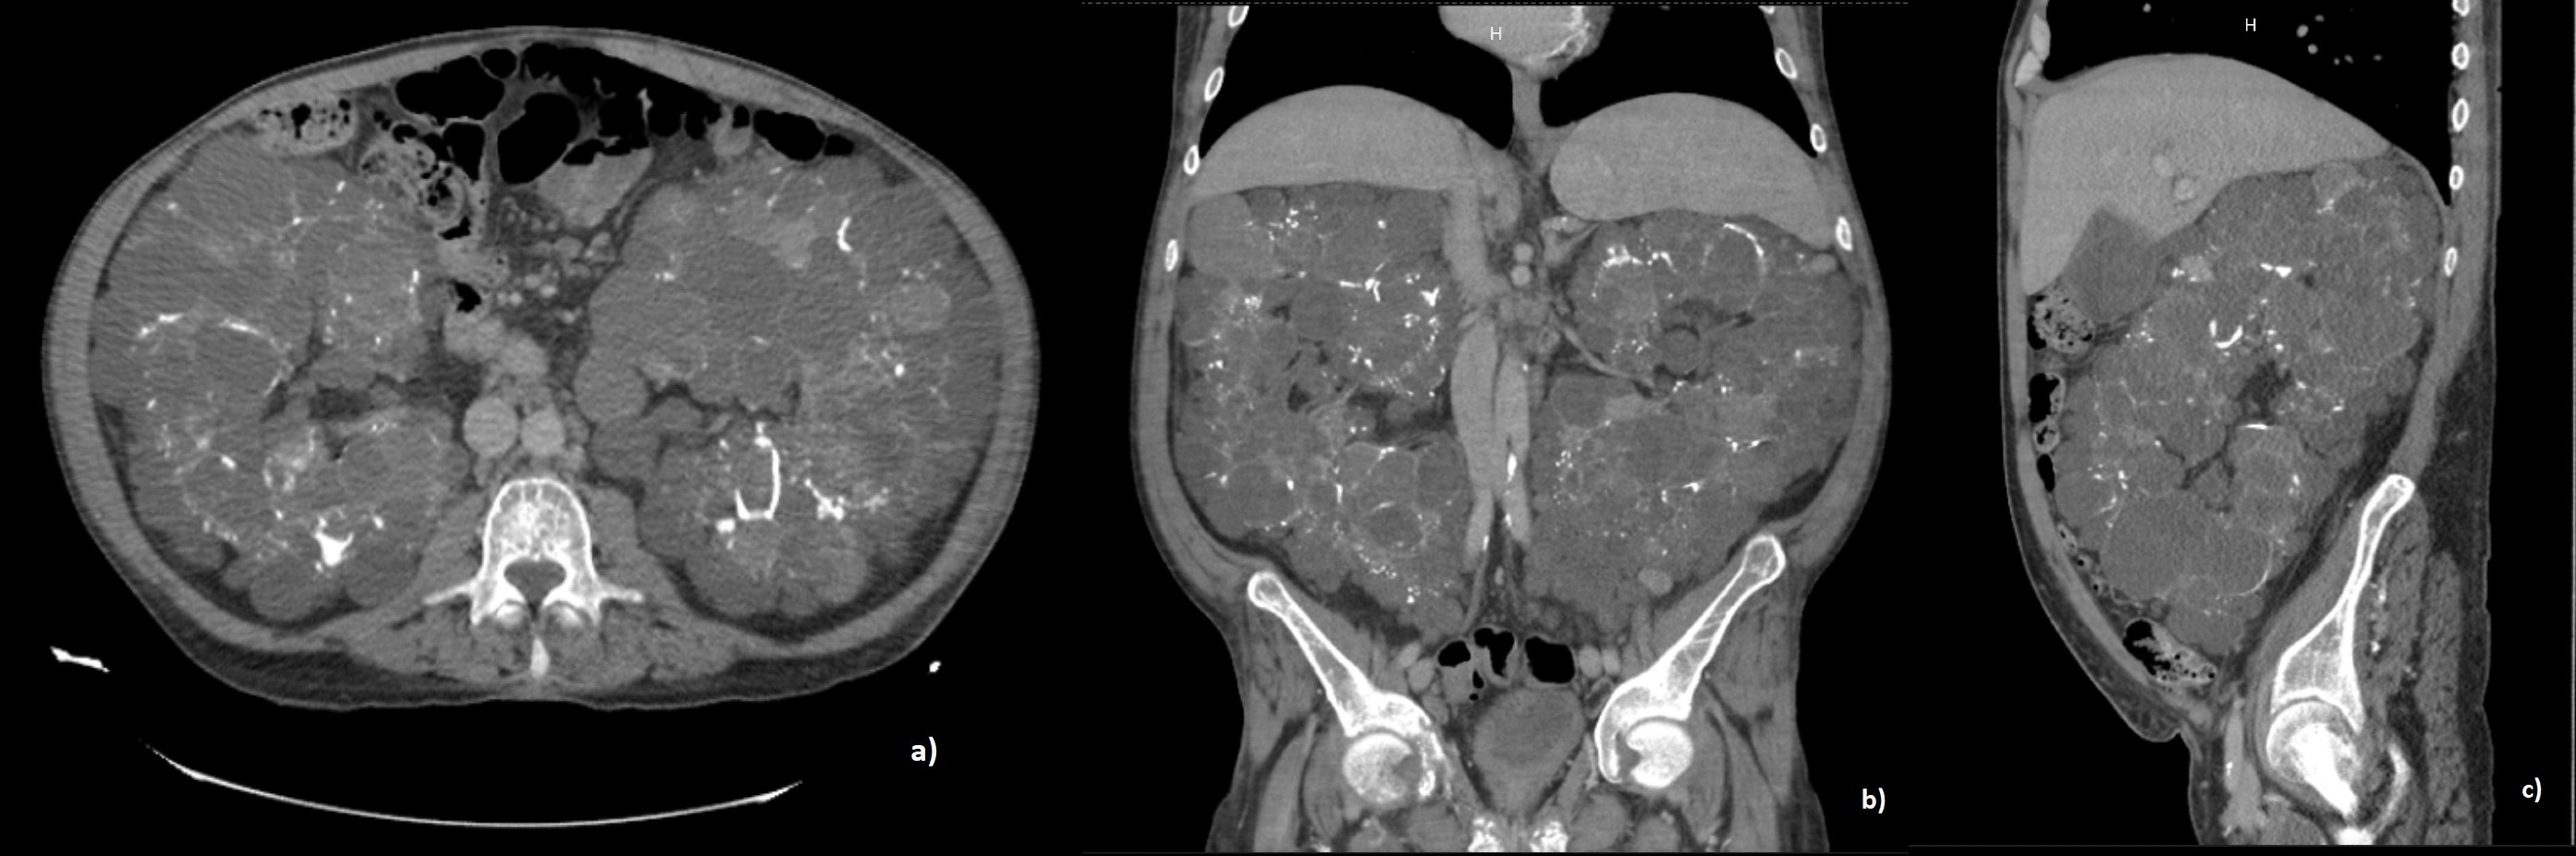

We present the case of a 42-year-old male with a history of stage V CKD diagnosed 5 years ago, receiving hemodialysis as a replacement therapy, secondary to confirmed ADPKD based on family history (father, paternal uncle, and brother with a history of ADPKD and stage V CKD), imaging, and clinical course. He was admitted to the hospital due to progressive increase in abdominal girth and generalized abdominal pain and in the lumbar region, as well as exertional dyspnea for the past 4 months. Pulse oximetry showed 91% saturation, with no evidence of cardiopulmonary compromise, only palpable renal masses in the abdomen without ascites. Laboratory tests revealed grade II anemia (hemoglobin 10.1g/dl [12 - 14 g/dl]) and blood chemistry showed impaired renal function tests (creatinine 8.7mg/dl [0.4 - 1.2 mg/dl], urea 72.1 mg/dl [12 - 54 mg/dl], blood urea nitrogen 33.7 mg/dl [6 - 20 mg/dl]) without other abnormalities. Abdominopelvic CT scan was performed, revealing massive bilateral polycystic renomegaly (Figure 1). The urology department informed the patient about the indication for bilateral laparoscopic nephrectomy due to symptomatic massive renomegaly, however, the patient declined the surgical procedure for personal reasons. Supportive measures were provided, including supplemental oxygen via nasal cannula, analgesia, and continued hemodialysis sessions following contrast study with clinical improvement. As there was no other indication for hospitalization to avoid nosocomial infections, the patient was discharged and referred to the urology outpatient clinic for follow-up.